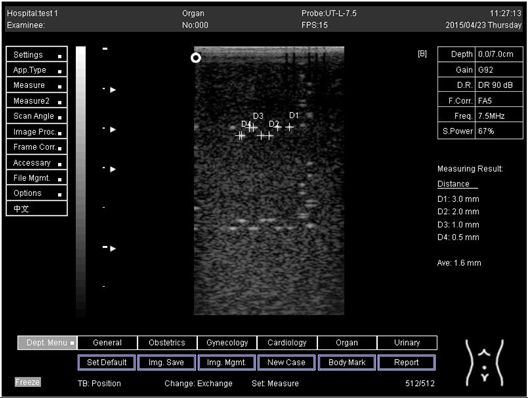

5.0 Lateral resolution

Biomimetics 07 00130 i012

D1 = 3.0

D2 = 2.0

D3 = 1.0

D4 = 0.5

Regarding phantom 2, only linear probes were applied. This is because phantom 2 is shorter than phantom 1, and the linear probe had a lower penetration setting compared to the curve probe. Therefore, a linear probe is more suitable for the phantom. Based on the results recorded on phantom 2, axial and lateral resolution measurements were still under an acceptable value since the percentage difference between the actual distances was less than 2% (Table 6).